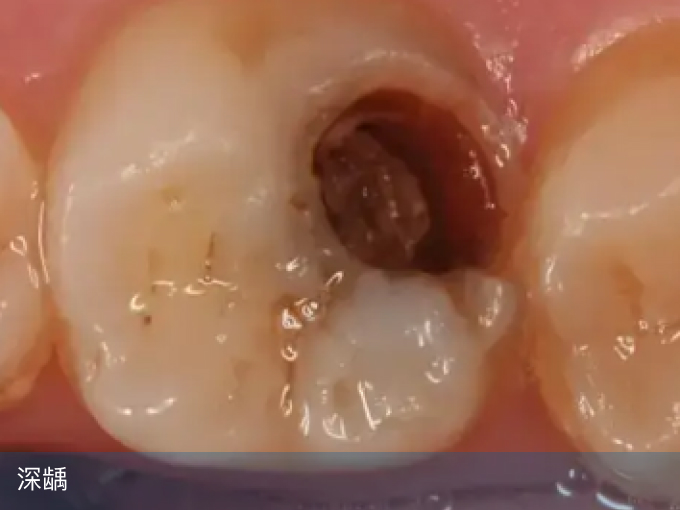

3、深龋

龋坏已经达到牙本质深层,甚至接近牙髓腔,进食时可出现明显疼痛,不仅需要补牙,而且需要进行垫底、安抚等处理,费用会稍微高一些,可以达到300-800元。